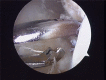

Material and methods: Of the 22 patients who were treated; 18 males and 4 females, and aged from 17-42 years (mean 28 years). All patients presented a history of more than three ankle sprains in the last two years and presented positive anterior drawer and talar tilt test of the ankle in the physical examination. We perform an anterior arthroscopy of the ankle in order to treat asociated disease and then we performed "All inside¨ lateral ligament repair through two portals (anteromedial and anterolateral) using an anchor knotless suture.

Conclusion: Several surgical procedures have been described during the last years in order to treat chronic ankle instability. ¨All inside¨ lateral ligament reconstruction presents lower local morbidity than open procedures with few complications. Moreover, it is a reproductible technique, with high clinical success rate, few complications and relatively quick return to sports activities. A high knowledge of the anatomic landmarks should be essential to avoid unwated injuries.